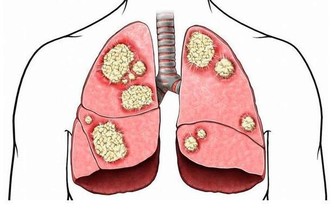

演變成肝癌的過程,是有著一個三部曲,那就是肝炎、肝硬化、肝癌的這樣子一個過程。其中,引起肝癌的誘因還有黃曲霉毒素,由於特別容易被忽視,尤其是在廚房裡面,那就需要特別引起人們的注意。

黃曲霉毒素是一種特別容易致癌的物質,能夠對人體內的肝臟組織造成一定的破壞,嚴重的情況下會導致肝癌甚至是死亡。廚房裡面的花生米還有玉米是最容易被黃曲霉毒素污染的食物,因為裡面是含有澱粉的成分,由於在運輸的過程中,遇到了潮濕還有發霉的情況,就會直接導致出現被黃曲霉毒素污染。及時是經過油炸或者是加熱的過程,也是很難能夠去除掉黃曲霉毒素。